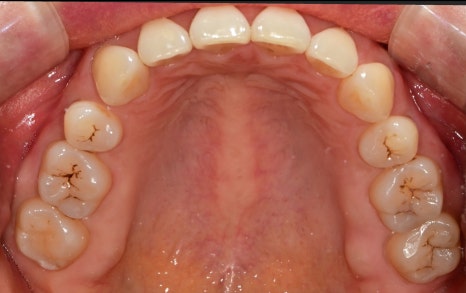

위에서 찍은 사진을 봤을 때

앞니 쪽이 둥근 아치를 그리지 않고

평편한 곡선을 그리고 있습니다.

이렇기 때문에 앞니가 안쪽으로 말려 들어가 보이고요